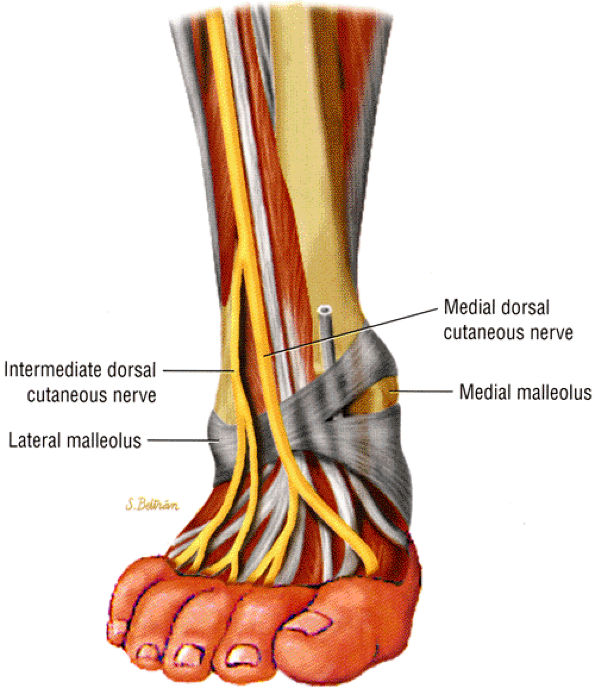

of the lower leg and dorsum of the foot with sparing of the first web space (innervated by the deep peroneal nerve). The pain is worsened with activity. Focal swelling, point tenderness, and exacerbation of symptoms with pressure occur approximately 10 to 12 cm above the ankle joint, where the nerve exits the deep fascia. When muscle herniation is the causative agent, a focal mass accentuated by resisted dorsiflexion may be seen.24 Prior trauma, particularly chronic ankle sprain, has been noted in approximately 25% of patients with superficial peroneal neuropathy. The neuropathy is most likely related to traction and stretching of the nerve.2 Impingement on the nerve following prior anterior compartment fasciotomy has also been described.